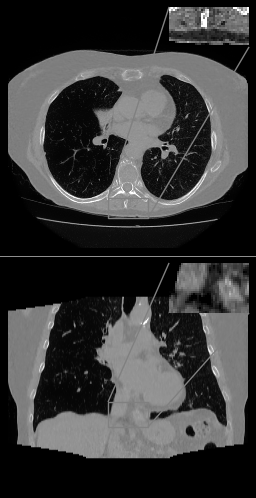

Refer to caption

(a)

(b)

(c)

(d)

Figure 2: (a) Axial (top) and coronal (bottom) slices of thorax CT, HU range=(-1000, 800) and (-150, 250) for ROI, (b) U-net (c) \partialU-net, (d) LIRE++

We perform extensive evaluation of LIRE++ and the baselines using image quality metrics such as PSNR and SSIM, which are computed for attenuation values, as well as MAE in Hounsfield Units due its importance for radiotherapy applications.

In Table 1 we report these metrics on the thorax & pelvic test set, and the corresponding box plots are provided in Figure 1. All metrics are computed for the full field of view region, i.e., the voxels which are present in at least half of the projections, which coincides with the field of view given by FDK and TV methods. Table 1 also contains mean total inference times per volume on NVIDIA A100 accelerator and the parameter counts, where in case of FDK and TV the parameter count of scatter pre-correction U-net is provided. In case of TV reconstruction, high inference time is partially due to multiple CPU-GPU memory transfers in ODL. Examples of thorax image slices of a ground truth image and the corresponding reconstructions from baselines and LIRE++ are presented in Fig. 2. Similarly, pelvic & abdominal image slices are presented in Fig. 3. The image samples demonstrate particularly well that LIRE++ is superior in reproduction of these soft tissue details which appear blurred in the baselines. Field-of-view in the reconstructions given by LIRE++ and \partialU-net is increased since the training loss is optimized over all voxels which are present in at least one projection. Extended FoV reconstruction quality for the voxels which are observed in at least one projection, but less than half of all projections, is slightly higher in LIRE++ reconstructions compared to \partialU-Net by appoximately 1 dB higher PSNR.